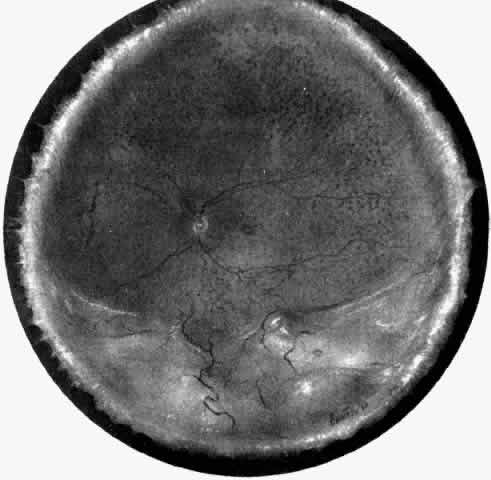

Fig. 1. Painting of the ophthalmoscopic features of uveal effusion syndrome. There is a diffuse pigmentary disturbance in a dot, blot, or linear configuration and an annular ciliochoroidal effusion with secondary inferior retinal detachment.

The presence of certain clinical characteristics may assist in the diagnosis of a ciliochoroidal effusion (Table 1). One clinical feature is choroidal edema. Choroidal edema may resemble a retinal detachment to a hasty observer; however, darkness of the uvea, lack of tremulousness, and normal retinal vessels indicate a probable uveal process (Fig. 1). The effusion may extend under the pars plana, allowing visualization of the ora serrata without scleral depression (Fig. 2).9 As shown in Figure 2, the surface of the elevation is convex and smooth, with a solid appearance and a homogeneous grayish color. A shallow anterior chamber and a low intraocular pressure may also suggest the diagnosis. Myopia in the presence of anterior displacement of the lens-iris diaphragm may be another diagnostic clue.10,11

In a chronic ciliochoroidal effusion, breakdown of the blood-ocular barrier at the level of the retinal pigment epithelium (RPE) may occur, leading to a nonrhegmatogenous retinal detachment characterized by shifting subretinal fluid. The protein content of this fluid may be more than three times greater than that of plasma, causing it to shift to a dependent position as the eye and head move.21 The amount of subretinal fluid increases as the chronicity of the effusion increases. A total retinal detachment may result, making the detection of shifting fluid difficult. Linear areas of RPE hypertrophy and hyperplasia may also be observed in chronic effusions (Fig. 3). These streaks, noted by Verhoeff,22 suggest a chronic and recurrent process.

Ciliochoroidal effusions may have an annular, lobular (Fig. 4), or flat (Fig. 5) ophthalmoscopic appearance. Annular effusions occur around the ciliary body and peripheral choroid. Lobular effusions are large hemispheric detachments that bulge toward the center of the globe. Flat effusions are most often apparent in isolated peripheral choroidal areas, where local structures limit fluid extension. A local stimulus, such as a limbal incision, can lead to suprachoroidal edema, even in remote areas, by way of free dissection of fluid. Occasionally, patients will present with coexisting ciliochoroidal effusion and rhegmatogenous retinal detachment.23–25 The retinal hole may be hidden in the choroidal mounds. Such detachments tend to occur in older patients who have a history of previous ocular surgery.